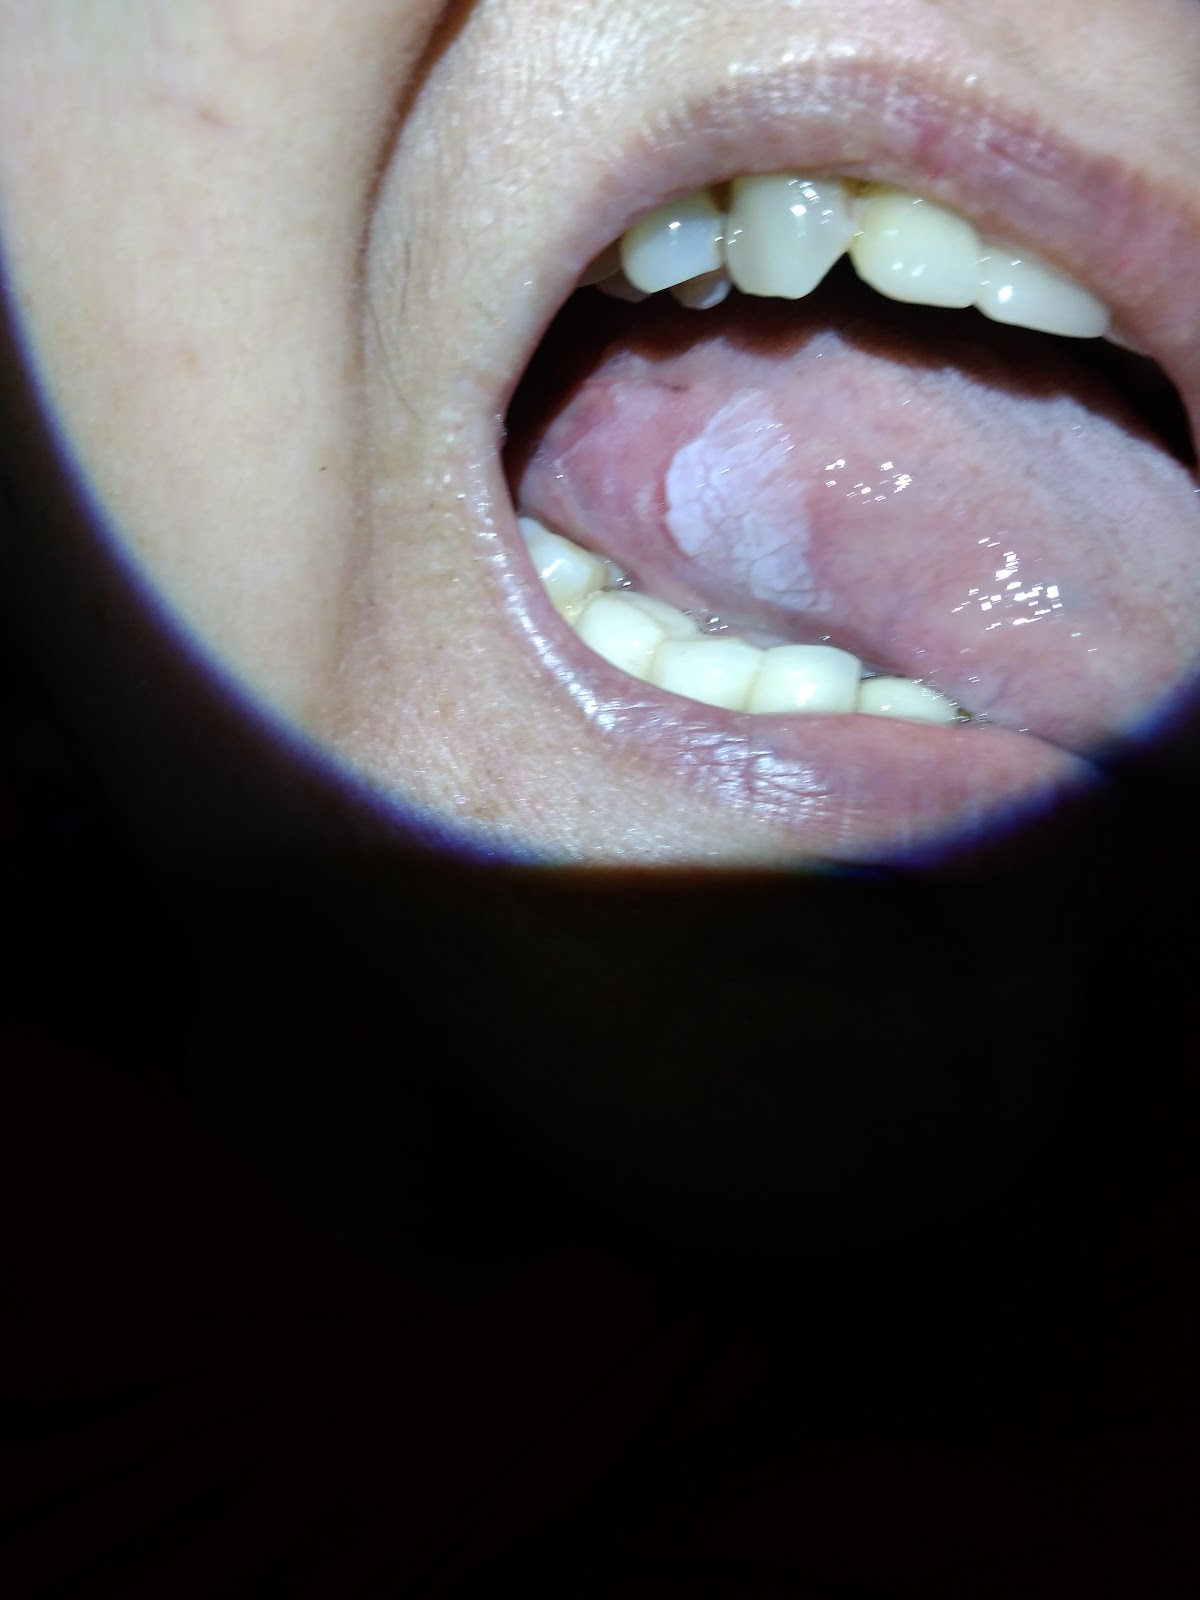

Laser Ablation Leukoplakia . Furthermore, the laser excision technique was found to be superior to laser. A clinical trial published by romeo et al. (2020) investigated the efficiency of co 2 laser ablation of oral leukoplakia on 30 patients (with a total of 33 oral leukoplakia. The study concluded that diode laser is an effective surgical treatment modality for treating leukoplakia. Oral leukoplakia (ol) is a white lesion with high potential of recurrence and malignant transformation. Laser therapy is one of the common treatment modalities for oral leukoplakia (olk). Based on the depth of tissue removed and the presence of dysplastic features, leukoplakia can be treated by two techniques. Treatment modalities for ol include scalpel excision, laser therapy, cryotherapy, topical application of bleomycin and vitamin a,. The pooled recurrence rate of olk received laser therapy.

Treatment modalities for ol include scalpel excision, laser therapy, cryotherapy, topical application of bleomycin and vitamin a,. Oral leukoplakia (ol) is a white lesion with high potential of recurrence and malignant transformation. Laser therapy is one of the common treatment modalities for oral leukoplakia (olk). Furthermore, the laser excision technique was found to be superior to laser. Based on the depth of tissue removed and the presence of dysplastic features, leukoplakia can be treated by two techniques. The pooled recurrence rate of olk received laser therapy. (2020) investigated the efficiency of co 2 laser ablation of oral leukoplakia on 30 patients (with a total of 33 oral leukoplakia. A clinical trial published by romeo et al. The study concluded that diode laser is an effective surgical treatment modality for treating leukoplakia.

Laser Ablation Leukoplakia Treatment modalities for ol include scalpel excision, laser therapy, cryotherapy, topical application of bleomycin and vitamin a,. Oral leukoplakia (ol) is a white lesion with high potential of recurrence and malignant transformation. A clinical trial published by romeo et al. The pooled recurrence rate of olk received laser therapy. The study concluded that diode laser is an effective surgical treatment modality for treating leukoplakia. Furthermore, the laser excision technique was found to be superior to laser. Treatment modalities for ol include scalpel excision, laser therapy, cryotherapy, topical application of bleomycin and vitamin a,. (2020) investigated the efficiency of co 2 laser ablation of oral leukoplakia on 30 patients (with a total of 33 oral leukoplakia. Based on the depth of tissue removed and the presence of dysplastic features, leukoplakia can be treated by two techniques. Laser therapy is one of the common treatment modalities for oral leukoplakia (olk).